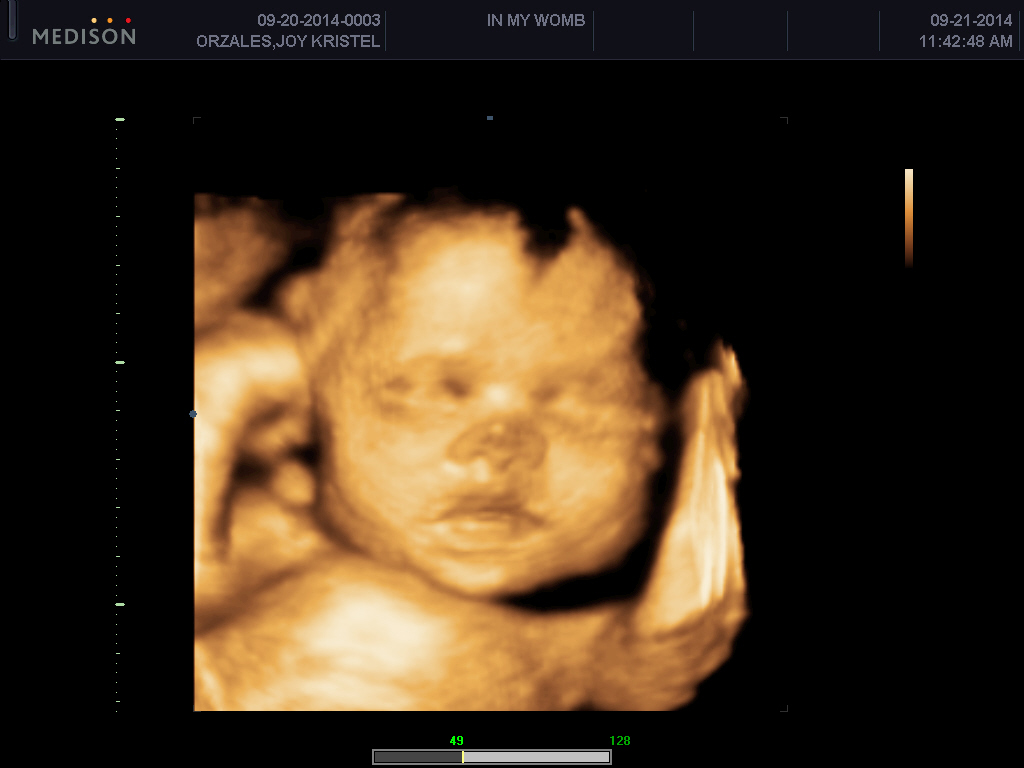

It was the most stressful part of this pregnancy. It started when we had a 3D4D ultrasound of our baby boy. The sonologist said that I should contact my OB regarding the femur length and amniotic fluid. So I txted my OB and she instructed me to have an ultrasound at St. Luke’s Global.

True enough, the amniotic fluid is slightly elevated. It’s within the high normal limits but the sonologist there said that the femur length was just fine. I consulted my OB regarding the findings and she said I will be monitored every two weeks for my fluid. She also said I should have a glucose tolerance test to check for diabetes. It took me 2 hours to finish my OGTT with four blood extractions and urine catch. Thank goodness the needle was just small that I managed to endure the extraction.

So the OGTT result came out negative. During my next check up, I was again asked to have another ultrasound to monitor the fluid. This time, the sonologist said that baby’s brain fluid was also within the high normal limits. When I went to my OB for the report, she referred me to a high risk pregnancy OB, Dr. Elisa Cornelio. So I have two OB doctors now, one is my main and the other one is for high risk pregnancy.

I went to see Dr. Cornelio for consultation as advised by my OB. When I handed her my ultrasound reports and Dr. Abaya’s referral letter, she checked my baby via her ultrasound unit. She said the fluid inside baby’s brain is just normal. She normally doesn’t mention it to her patients to avoid stress and panic. Although she said it is really elevated, there’s nothing to worry about it. The baby is perfectly fine. She said that her patients with that kind of fluid in brain usually have healthy babies. So me and my husband were able to breathe after that consultation. It took us three weeks, I think, before we were relieved.